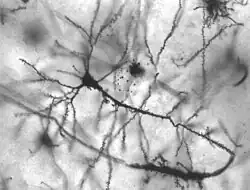

Durante la maduración se produce un proceso que implica la degeneración progresiva y/o la muerte de las neuronas. Este proceso, que puede ser normal y natural durante el envejecimiento normal, involucra a las células fundamentales del tejido nervioso y a sus componentes internos, que son los que impiden efectividad en la conducción de información en el cerebro humano, con la consecuente disminución de las funciones cognitivas. Así, durante el envejecimiento normal se limitan funciones cerebrales en la zona afectada pero también pueden aparecer distintas patologías neurológicas en el ser humano, llamadas enfermedades neurodegenerativas.[1][2][3]